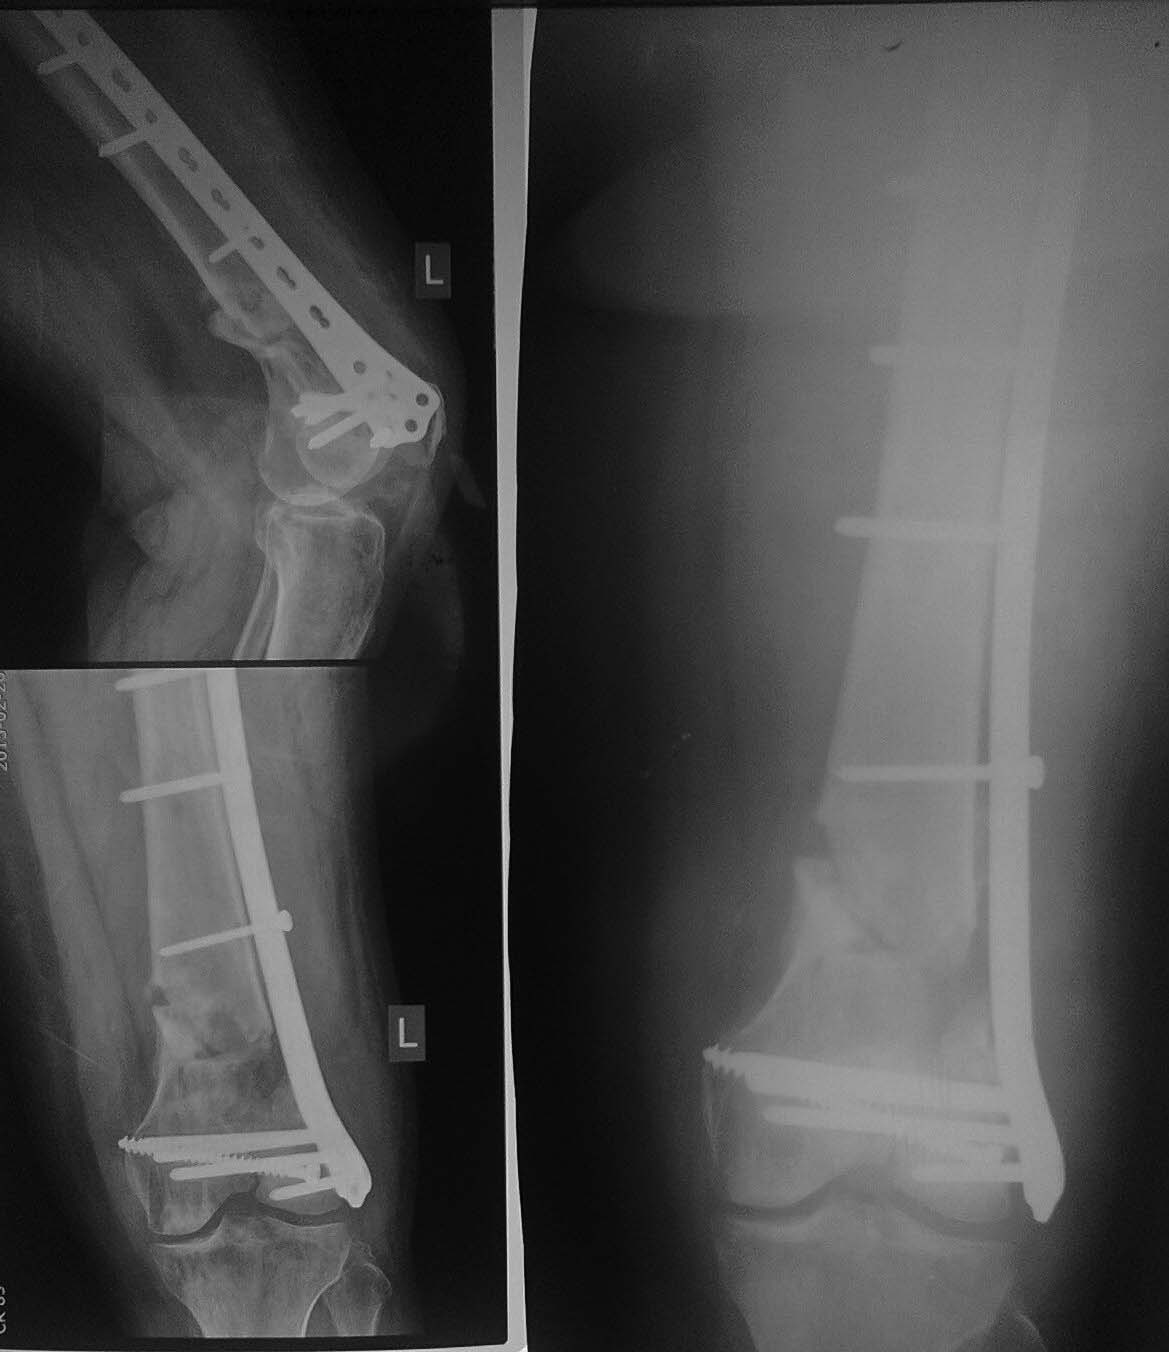

Операция 16.09.14.-Открытая репозиция мыщелков бедренной кости, остеосинтез винтом, закрытая аппаратная репозиция, малоинвазивный остеосинтез бедренной кости опорной мыщелковой пластиной на винтах с угловой стабильностью с контролем под С-дугой(снимок 2).

Сегодня пришла на консультацию (снимок 3). С ее слов: в своей поликлинике ей запрещают до сих пор нагрузку, аргументируя несращением.

Самостоятельно была на консультации в институте травматологии и ортопедии в областном центре, где ей предложили выполнить реостеосинтез с костной пластикой. Стоит ли торопиться с оперативным лечением или дать походить с возрастающей нагрузкой- возможно произойдет полная консолидация? Спасибо всем откликнувшимся!